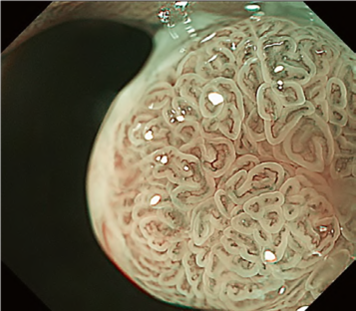

Predicting invasion depth of superficial esophageal squamous cell carcinoma is crucial in determining the precise indication for endoscopic resection (ER) because the rate of lymph node metastasis increases in proportion to the invasion depth of the carcinoma. Previous studies have shown a close relationship between microvascular patterns observed by magnifying endoscopy and invasion depth of the superficial carcinoma. Although there were two major classifications, Inoue and Arima, the Japan Esophageal Society (JES) integrated the two classifications and simplified it and developed a new magnifying endoscopic classification for the characterization and predicting invasion depth of superficial esophageal squamous cell carcinomas (SESCCs). This is essential for developing a treatment strategy for SESCC, in particular the indication for ER. Therefore, in this classification, morphological types of microvessels are classified into two categories of noncancerous [type A: normal epithelium, inflammation, and squamous intraepithelial neoplasia (SIN)] and cancerous (Type B: SCC) lesions. The cancerous types of microvessels corresponding to SESCCs are subclassified into three groups based upon an indication for ER as follows: an absolute indication type (Type B1: T1a-EP or T1a-LPM), a relative indication type [Type B2: T1a-MM or T1b-SM1(tumor invades the submucosa to a depth of 200 μm or less from the muscularis mucosa)], and a contraindication type [Type B3: T1b-SM2 (tumor invades the submucosa to a depth more than 200 μm)]. Diagnostic criteria of the JES classification are based on the degree of microvascular irregularity in the target lesion observed by magnifying endoscopy. Intrapapillary capillary loops (IPCL) are a basic unit of microvasculature in the stratified squamous epithelial layer. The microvascular irregularity is evaluated for the presence or absence of each of the following morphological factors: weaving (i.e., tortuosity), dilatation, irregular caliber, and different shape (i.e., various shapes). Microvessels are classified as type A if they have three or fewer factors (i.e., without severe abnormality; . Fig. 1a) and type B if they have all four (i.e., with severe abnormality). Type B is then subclassified into B1, B2, and B3 (. Fig. 1b–d, respectively) based on the running pattern or degree of dilatation of severely irregular microvessels. The definitions and schemas of type A and B vessels and predicted histology of invasion depth by type B vessels are summarized in . Table 1. A large scale validation study showed high overall accuracy (90.5%) of type B vessels of the JES classification. The most important auxiliary criterion in the JES classification is avascular area (AVA). AVA is defined as a low or no vascularity area surrounded by all subtypes of type B microvessels including B1 vessels. Diameters of AVA are positively correlated with sizes of histological cancer nest and the histological invasion depth of SESCC. Small (<0.5 mm), middle (0.5 ≤< 3 mm), and large (≤3 mm) AVA are suggestive of T1a-EP/ LPM, T1a-MM/T1b-SM1, and T1b-SM2, respectively. A key point to note is that any types of AVA (small, middle, and large) surrounded by B1 vessels are suggestive of T1a-EP or T1a-LPM SCC.